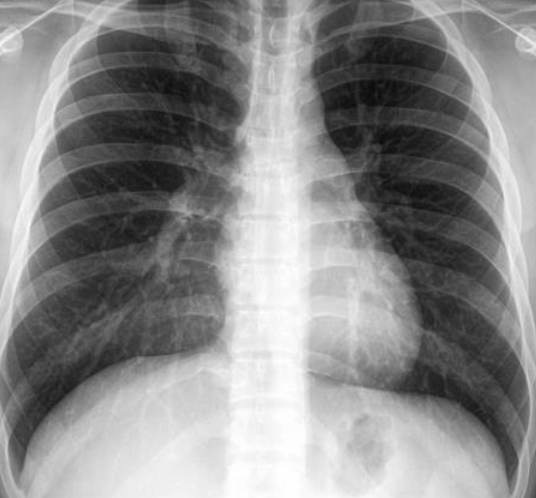

Patient with recurrent attacks of dyspnea and chest tightness after exercise. Clinical diagnosis bronchial asthma. Chest X ray is as follows:

Q1: in this chest x-ray normal or abnormal? Normal.

Q2: on chest auscultation, what added sounds can be heard in asthma? Wheeze.

Q3: Name any drug which can precipitate asthma? NSAIDS, Beta blockers.

Q4: You ordered spirometry for this pt. what will be the expected finding? FEV1 is reduced.

Q5: Name 2 clinical features of severe asthma? Z Can Not complete a sentence in one breath, Tachypnea, cyanosis

Q6: What ttt will you give in moderate to severe asthma? Name any 2. Bronchodilators, corticosteroids.